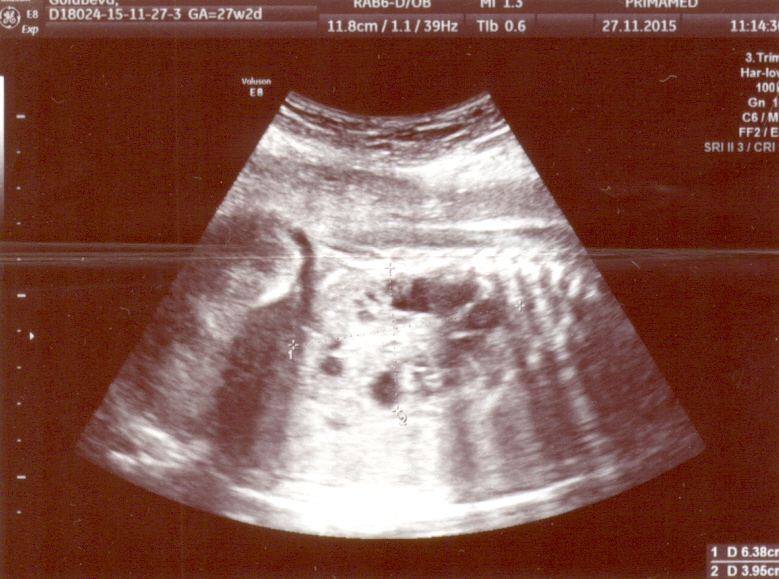

Спасибо доктор, немного утешили!Все станет ясно завтра-консилиум.И я так понимаю,что поликистоз все-таки,если можно так сказать лучше чем мультикистоз.А так почки увеличены правая-64*40,а левая-67*34,паренхима с множественными мелкокалиберными кистами.БПР 73мм,ЛЗР-96мм,ОГ-268мм,ОЖ-249мм ДБ-49мм.

Михаил Юдович,прикрепляю снимки.Заранее благодарна!Вы дали нам надежду и может сегодня ночью я посплю.Да кстати мне 39 лет и это мои 2 роды,первому ребенку 16 лет и никаких проблем с почками у него нет.Хотя у меня до 1-й беременности один раз были проблемы -в 1998году и что-то там было( 1 почка увеличена и раздвоена).Но после этого ни разу за 16 лет я про почки не вспоминала,еще у меня резус отрицательный у мужа положительный.Может какие-то из этих признаков повлияли на эту патологию?

3olg76uyar, Выскажу своё мнение, которое не является окончательным заключением, т.к. УЗИ надо видеть "в живую" Я думаю, это не мультикистоз, а другое, также очень тяжёлое заболевание. Это больше похоже на неонатальный тип поликистоза почек. Почки очень большие. Я смог разглядеть надпись - они по 6 см в длину. Это размер почек годовалого ребёнка. Паренхима в почках есть (что исключает мультикистоз), но она очень гиперэхогенная и высока вероятность продвинутой почечной недостаточности с рождения. Столь большие почки снизу давят на лёгкие и могут вызвать их недоразвитие. Подобный тип поликистоза почти всегда сопровождается фиброзом печени, который может быть пока не виден по УЗИ, но прогрессирует в течение нескольких лет после рождения.

Здравствуйте!Сегодня был консилиум и диагноз мультикистозная дисплазия обеих почек подтвердился.Правая почка-61*35,левая-65-32,ткань перенхимы почек представлена множеством анехогенных включений Д до 13мм. Мочевой пузырь 20*15.ИАЖ-8 см.Беременность 28 недель.При этом все остальные органы в норме без потологий.Следующий консилиум через 3 недели и я так понимаю шансов практически нет.